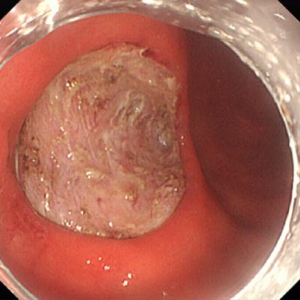

《胃ESDの実際》

食道表在癌、早期胃癌の治療法として当科では積極的にESDを行っています。ESDとは内視鏡的に使用可能な高周波メスを使って、粘膜下層のレベルで病変を剥がし取る手技です。早期の小さな癌に対しては今までも内視鏡治療が行われてきましたが、ESDにより従来の内視鏡治療法(EMR)では切除困難であった大きな病変や、瘢痕を認める病変を一括切除できるようになりました。体を切開することなく組織も温存できるため、患者の身体的負担が少ない低侵襲医療のひとつです。

食道ESDは年間約15例、胃ESDは年間約40例ほど行っております。